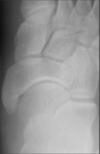

8

Q

What view is this?

A

Medial Oblique